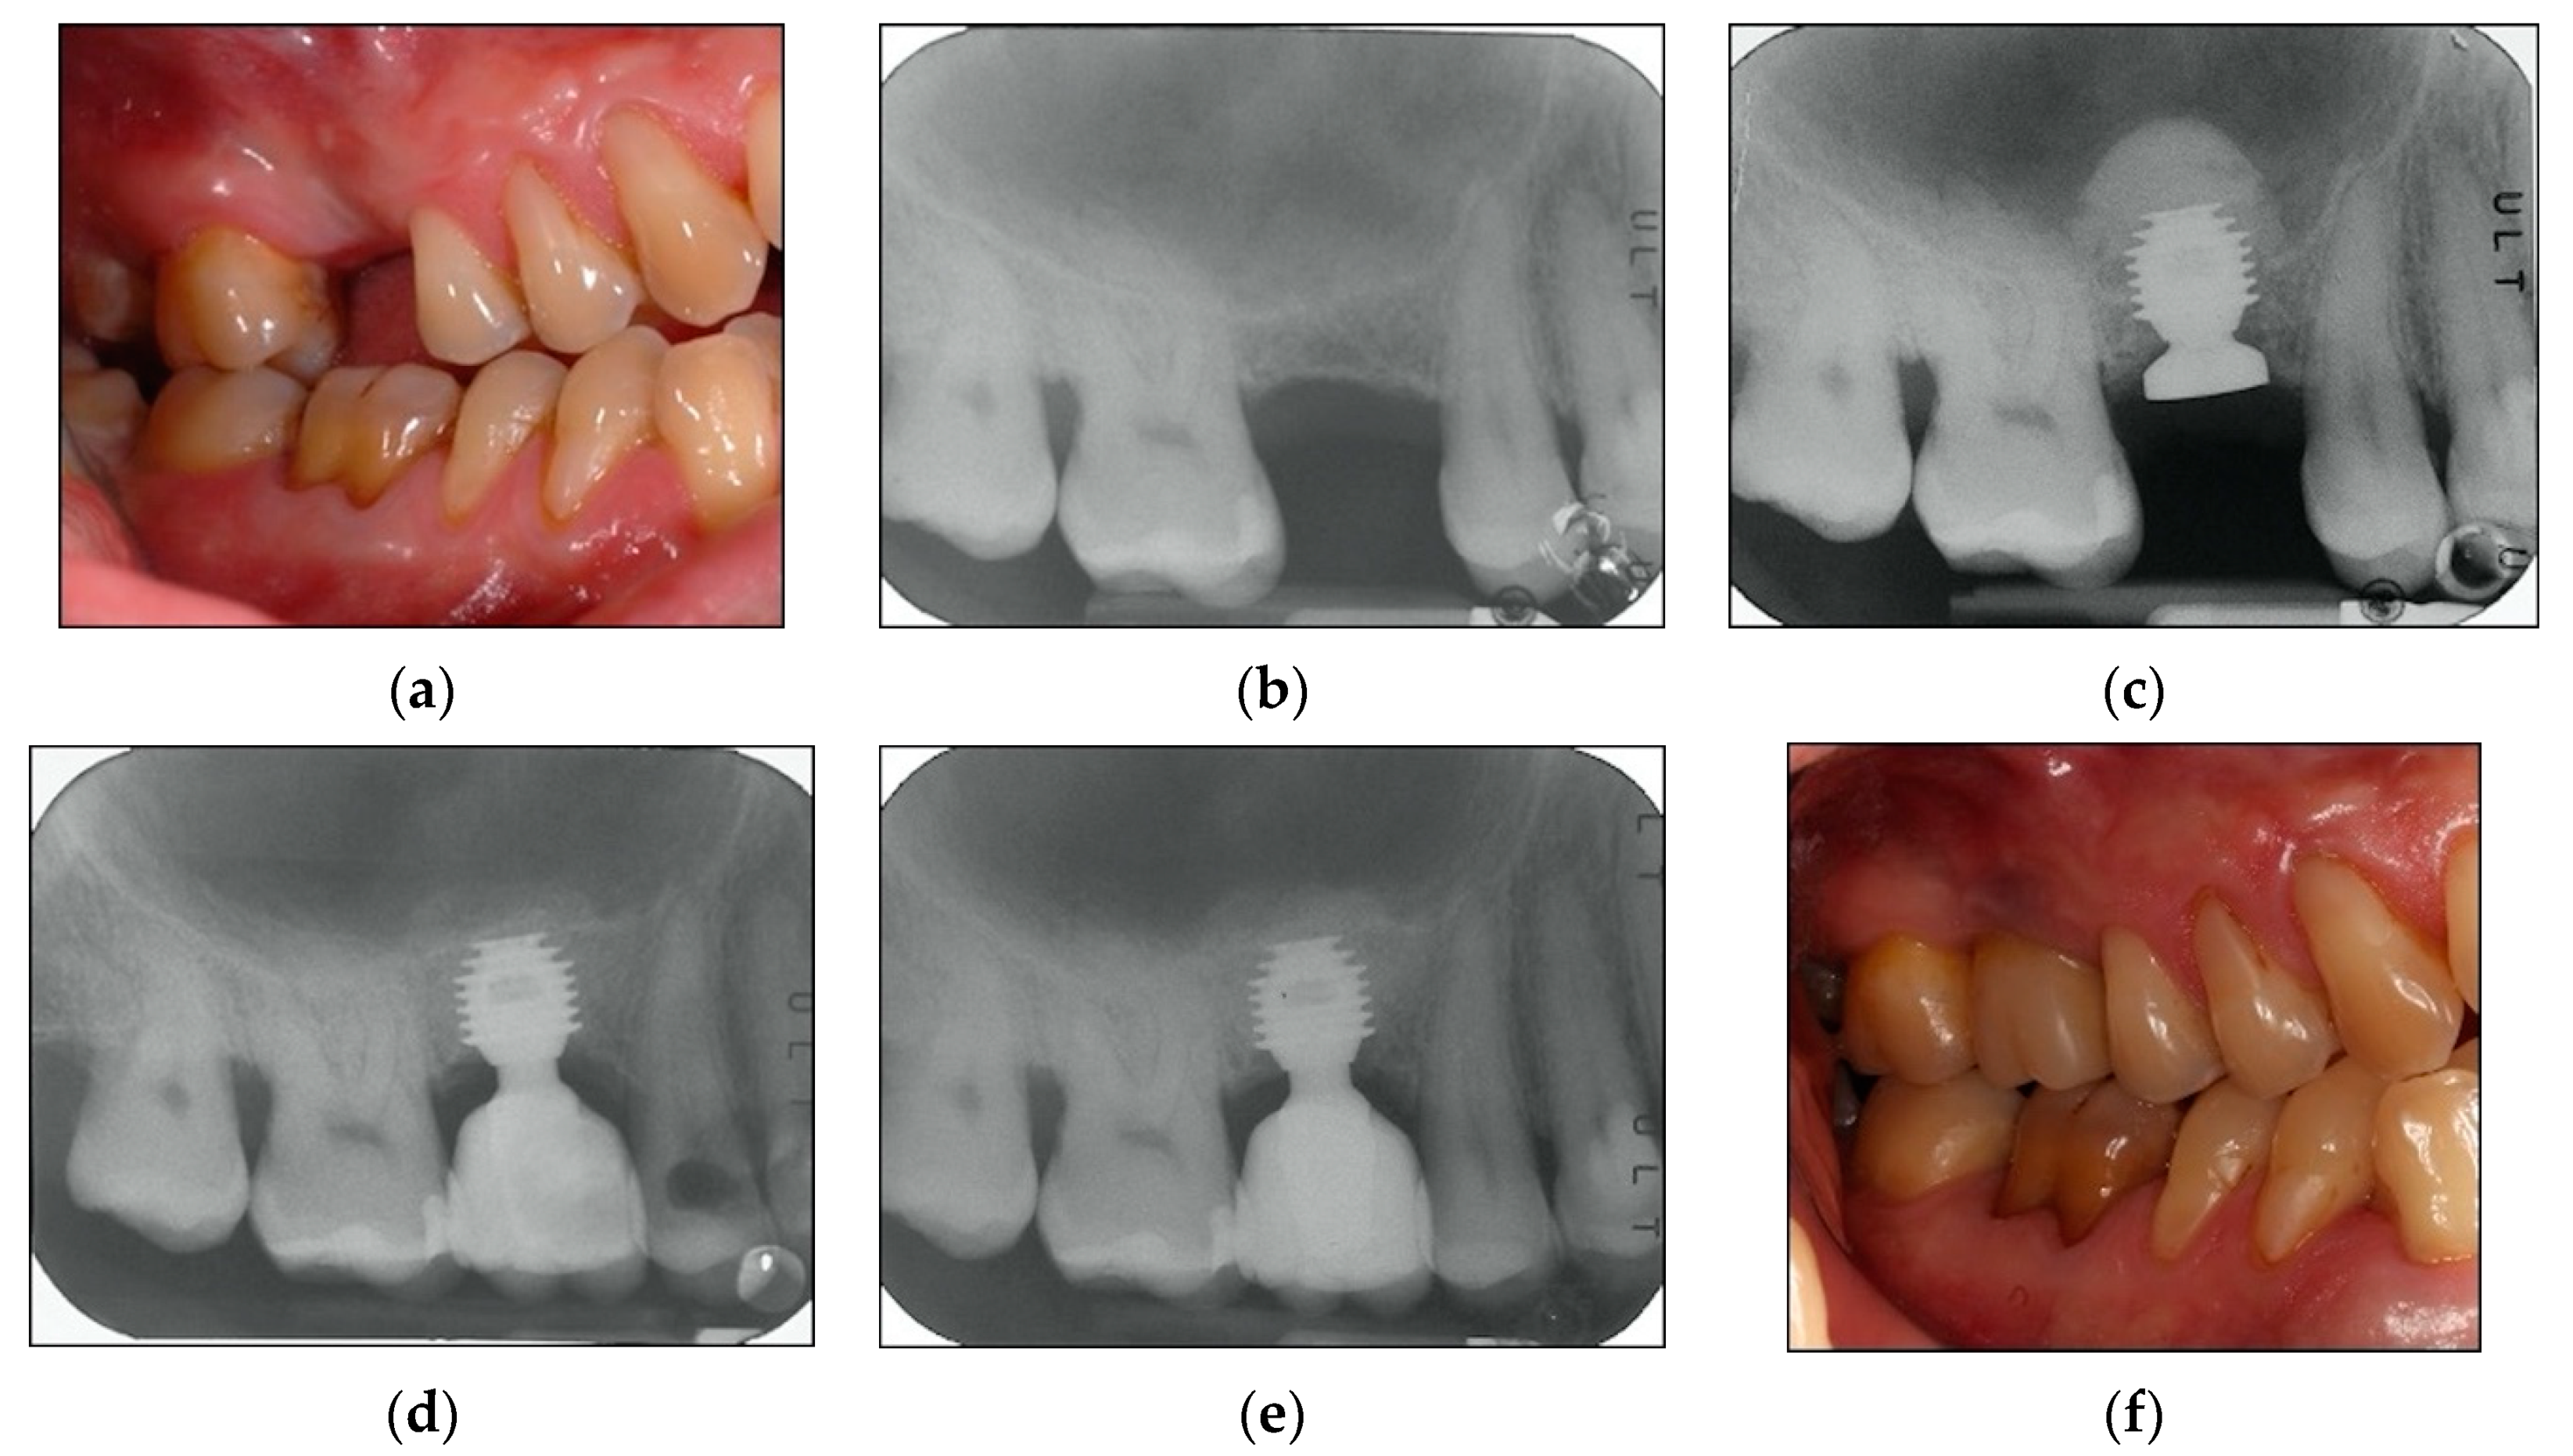

A maintenance program was designed to provide patients a professional oral hygiene session every four months [33] and home care procedures were reinforced. At each recall appointment, occlusion was assessed and adjusted as necessary; prosthetic restorations were checked for loosening, chipping, or other types of complications. Clinical assessment of peri-implant soft tissues and radiographic examinations were performed after three years of follow-up from loading time [29,30]. By way of illustration, Figure 2, Figure 3 and Figure 4 report some radiographic cases.

Figure 3. (af). Clinical case: Four implants placed in 1.4, 1.5, 1.6, and 1.7 sites. (a) Clinical photograph before implants placement. (b) Pre-operative radiograph before implants placement in sites 1.4, 1.5, 1.6, and 1.7. See minimal bone levels. (c) Radiograph obtained at time of implants placement. Two of the implants have sinus lift abutments. Augmented sinus visible. (d) Implants restored. Radiograph obtained at time of loading. (e) Radiograph obtained at the three-year follow-up. See stable bone levels both for sites with augmented sinus floor and for sites without it. (f) Clinical photograph at three-year follow-up. See stable clinical conditions.